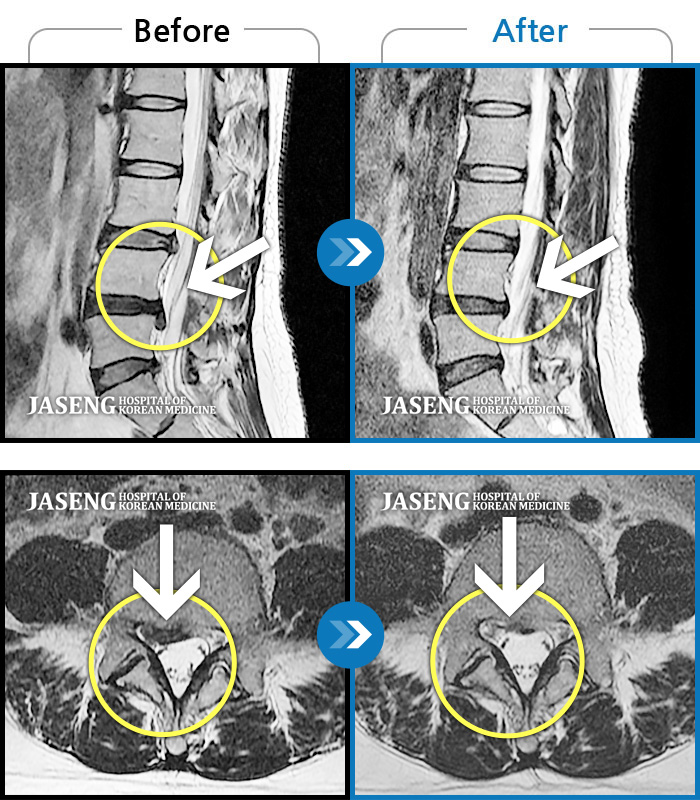

허리디스크

도움받은 사례

인천 · 조남훈 원장

재채기 하고 나서 다리에 힘이 안들어가요.

촬영시기

2021.11.10 ~ 2024.11.26

2024.12.04